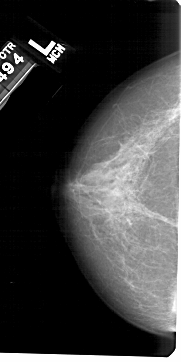

A_1520_1.RIGHT_MLO

LEFT_MLO LINES 5491 PIXELS_PER_LINE 2716 BITS_PER_PIXEL 12 RESOLUTION 43.5 NON_OVERLAY